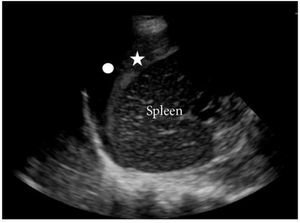

- Splenorenal

- Place probe in post ax line

- Pitfall: Look superior to spleen for fluid, not just splenorenal

- Troubleshooting: Slide probe as posteriorly as possible, have patient hold breath if able to